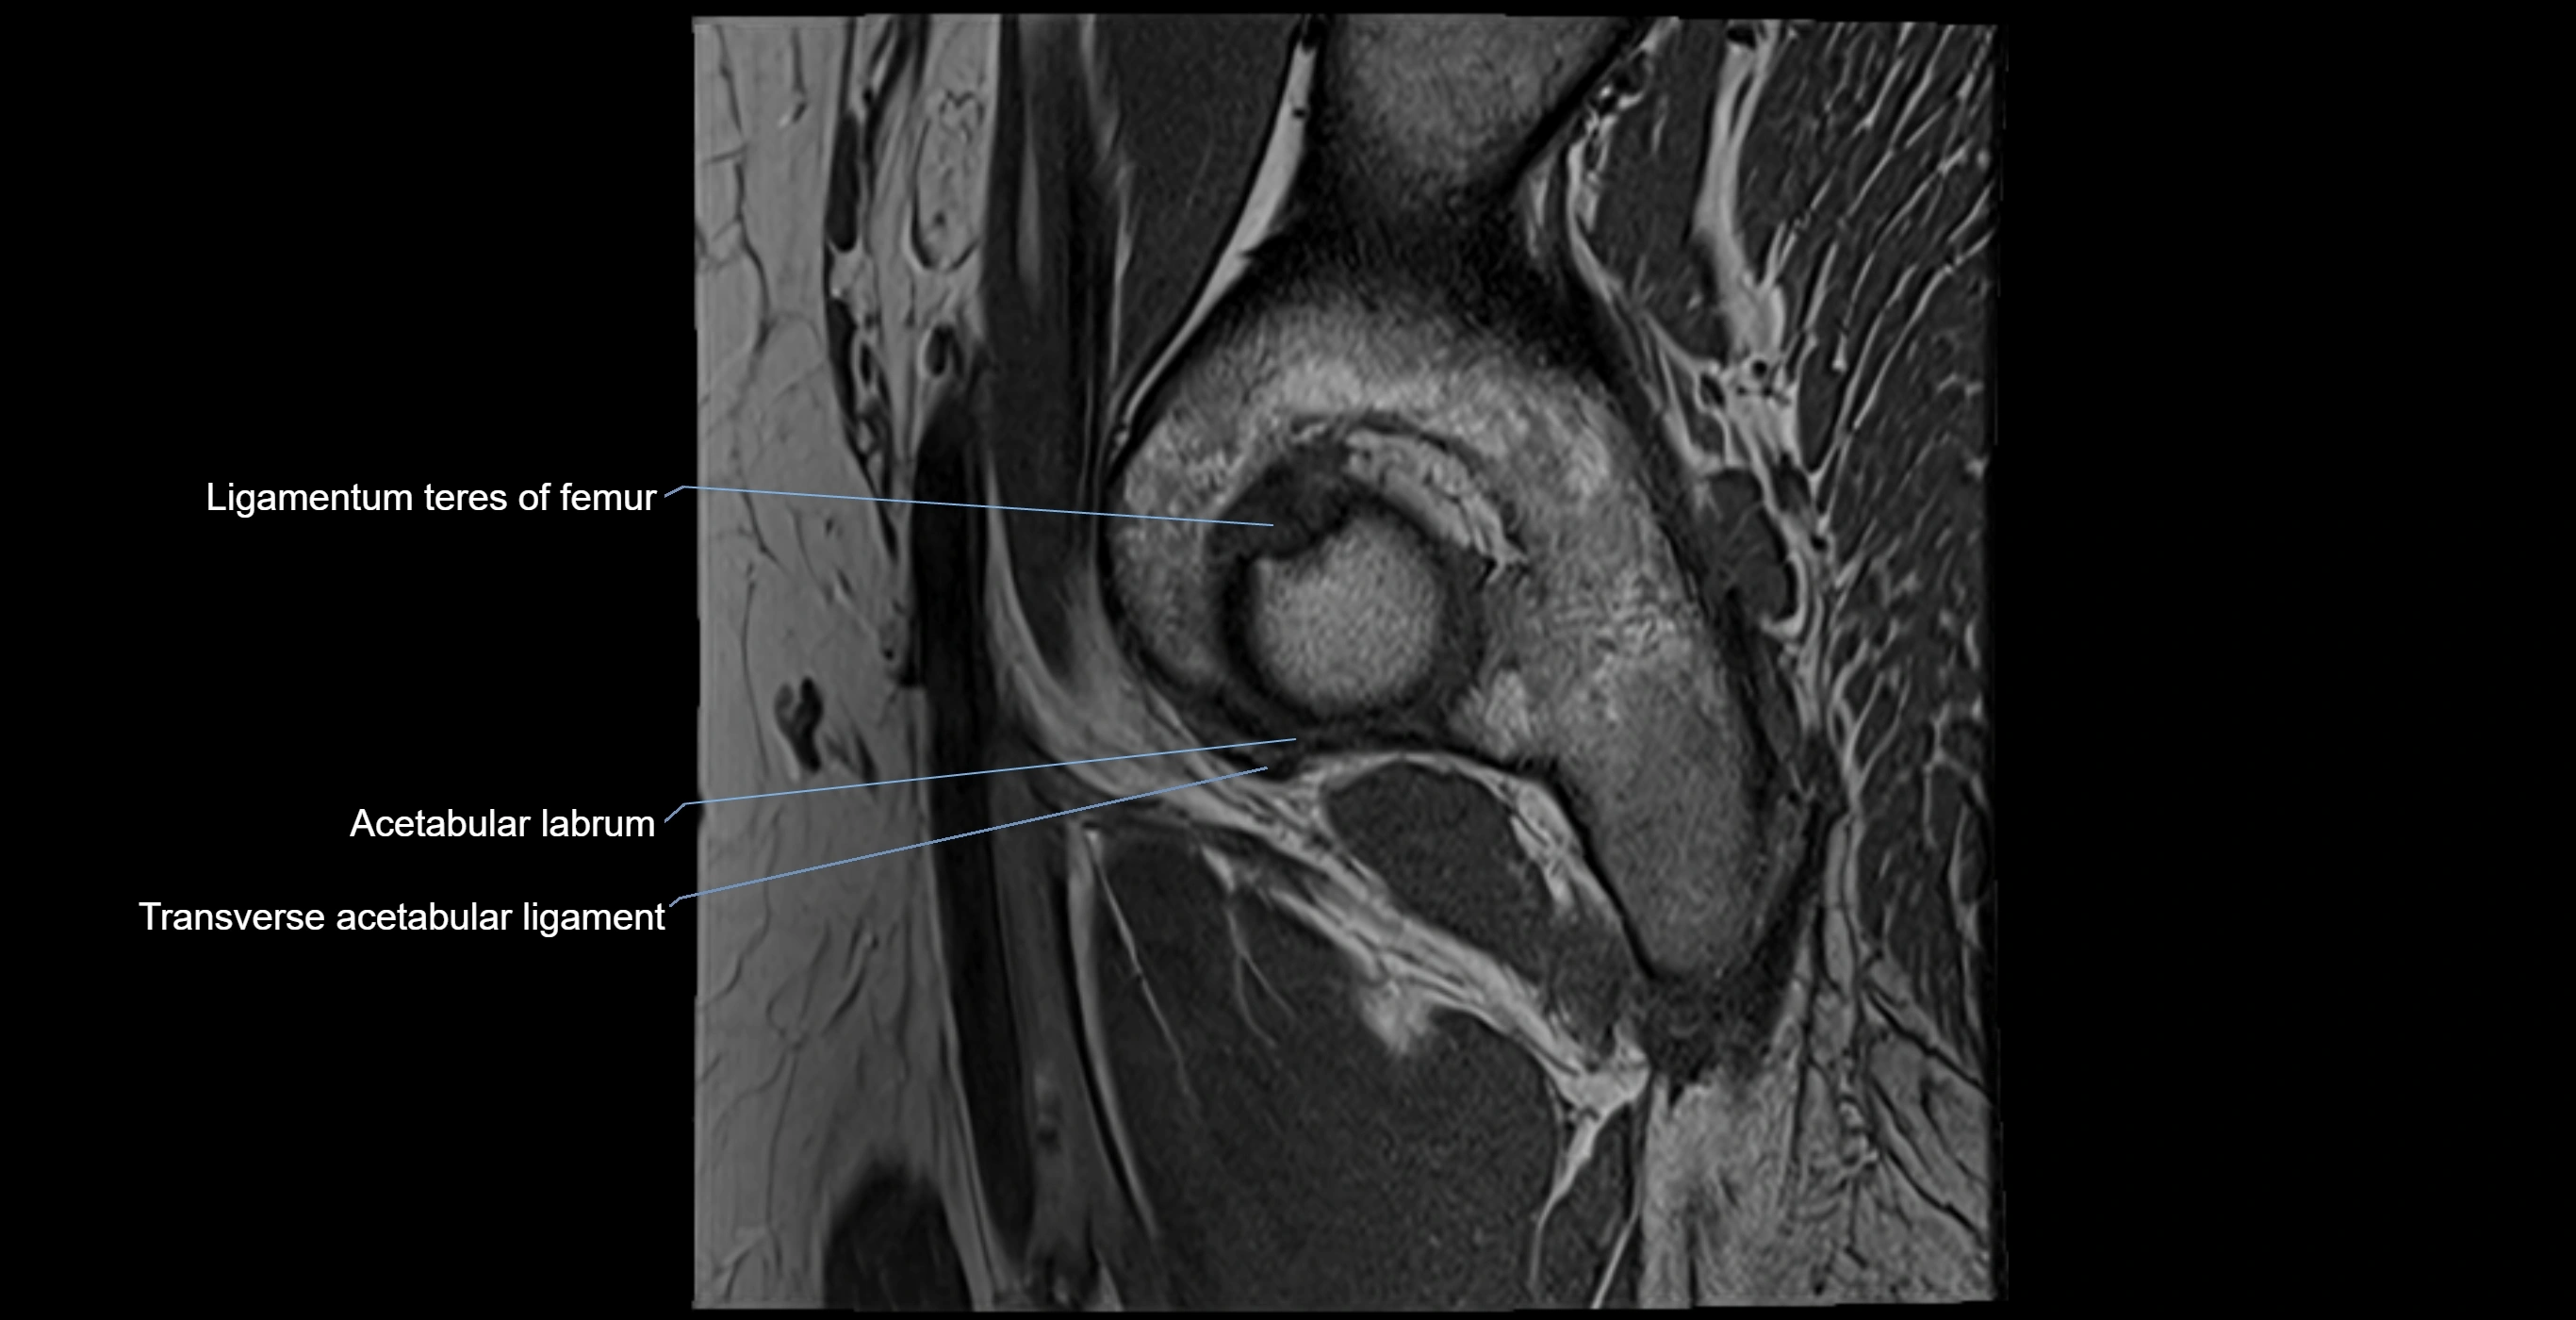

The acetabular labrum is a fibrocartilaginous ring that surrounds the rim of the acetabulum in the hip joint. It deepens the hip socket, increases joint stability, and maintains a suction seal that preserves negative intra-articular pressure. Structurally, the labrum transitions from hyaline cartilage of the acetabulum to dense fibrocartilage at its free edge.

It is triangular in cross-section, with its base attached to the acetabular rim and its apex projecting toward the femoral head. The labrum is most robust superiorly and anteriorly, where load bearing is greatest, and relatively thinner inferiorly.

Structure and Relations

• Superior and anterior labrum: thickest portions, stabilizing against anterior dislocation

• Inferior labrum: blends with the transverse acetabular ligament bridging the acetabular notch

MRI Appearance

T1-weighted images:

• Labrum: low signal intensity (dark)

• Surrounded by intermediate signal joint fluid (bright on arthrogram)

• Tears: linear or focal areas of intermediate-to-high signal interrupting labral continuity

T2-weighted images:

• Joint fluid: bright, making labral tears visible as fluid extending into or around labrum

• Degeneration: may show areas of increased signal within labrum

T1 Fat-Sat Post-Contrast (MR Arthrography):

• Normal labrum: remains dark

• Tears: contrast extends into the labrum or between labrum and acetabular rim

• Degeneration: irregular labral contour, heterogeneous enhancement in inflamed tissue